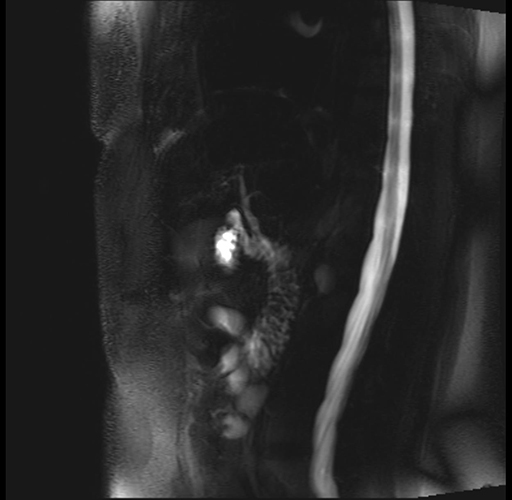

Imaging Analysis

Look through the patient's CT scan to identify any areas of concern for the necessary procedure.

Based on your CT findings, which issue(s) are present and would give reason for "planned slowing down moment(s)" in this case?

Considering a standard distal pancreatectomy procedure, what step(s) of the operation would you do differently in this case?